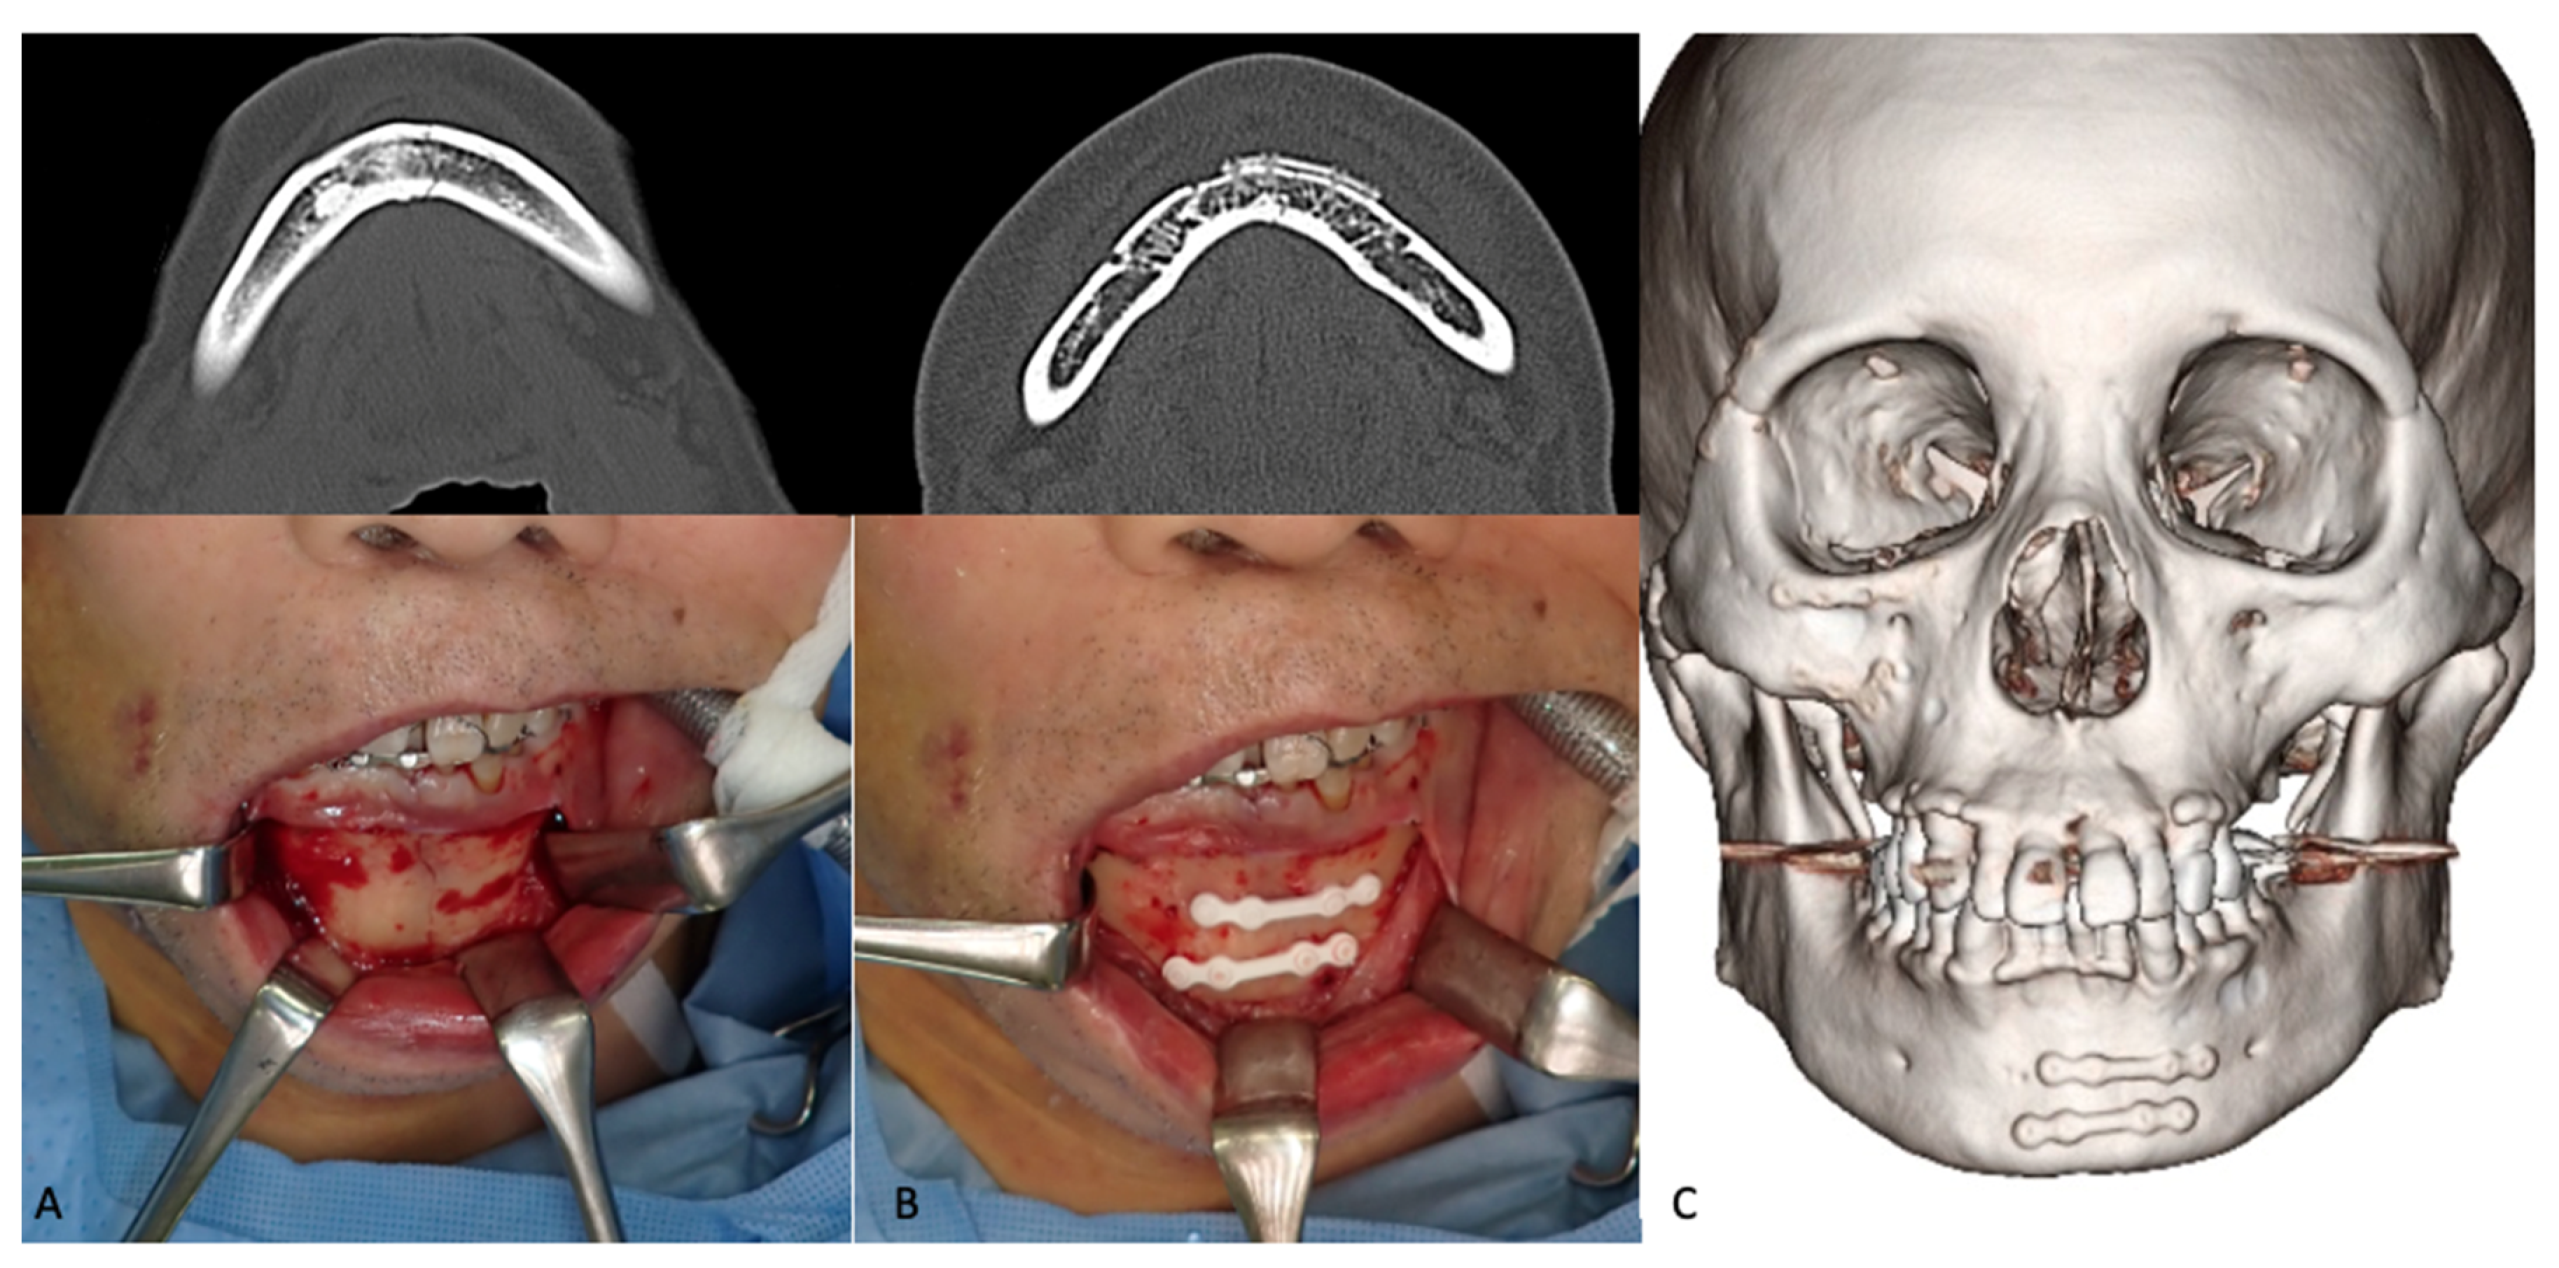

3.1.3. Mandibular Fractures

- Sukegawa, S.; Kanno, T.; Katase, N.; Shibata, A.; Takahashi, Y.; Furuki, Y. Clinical Evaluation of an Unsintered Hydroxyapatite/Poly-L-Lactide Osteoconductive Composite Device for the Internal Fixation of Maxillofacial Fractures. J. Craniofac. Surg. 2016, 27, 1391–1397. [Google Scholar] [CrossRef] [PubMed] [Green Version]

- Lee, S.J.; Park, E.S.; Nam, S.M.; Choi, C.Y.; Shin, H.S.; Kim, Y.B. Surgical Treatment of Mandible Fracture Using Unsintered Hydroxyapatite/Poly L-Lactide Composite Fixation System. J. Craniofac. Surg. 2019, 30, 2573–2575. [Google Scholar] [CrossRef]

- Song, I.-S.; Choi, J.; Kim, S.R.; Lee, J.-H. Stability of bioresorbable plates following reduction of mandibular body fracture: Three-dimensional analysis. J. Cranio-Maxillofacial Surg. 2019, 47, 1752–1757. [Google Scholar] [CrossRef]